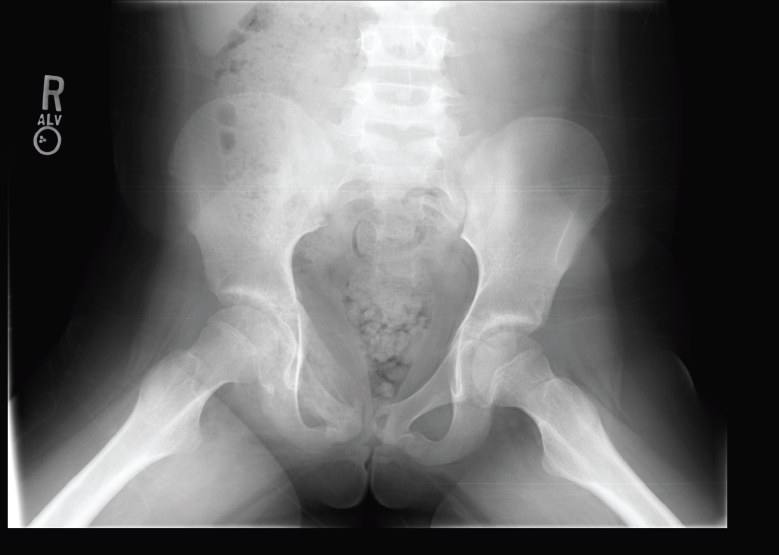

Radiographs obtained in the ED (Figures 1, 2, and 3) helped guide management and diagnosis.

Figure 3. Anteroposterior radiograph of the pelvis.

The radiograph of the girl’s pelvis (Figure 3) revealed onion-skin periostitis along the right superior pubic ramus. Computed tomography (CT) scanning of the pelvis was performed for further evaluation of the radiography findings. The CT images (Figures 4, 5 and 6) showed a permeative lesion that involved the entire right superior pubic ramus, with cortical destruction and onion-skin periostitis that were concerning for malignancy. The diagnosis of Ewing sarcoma was made.